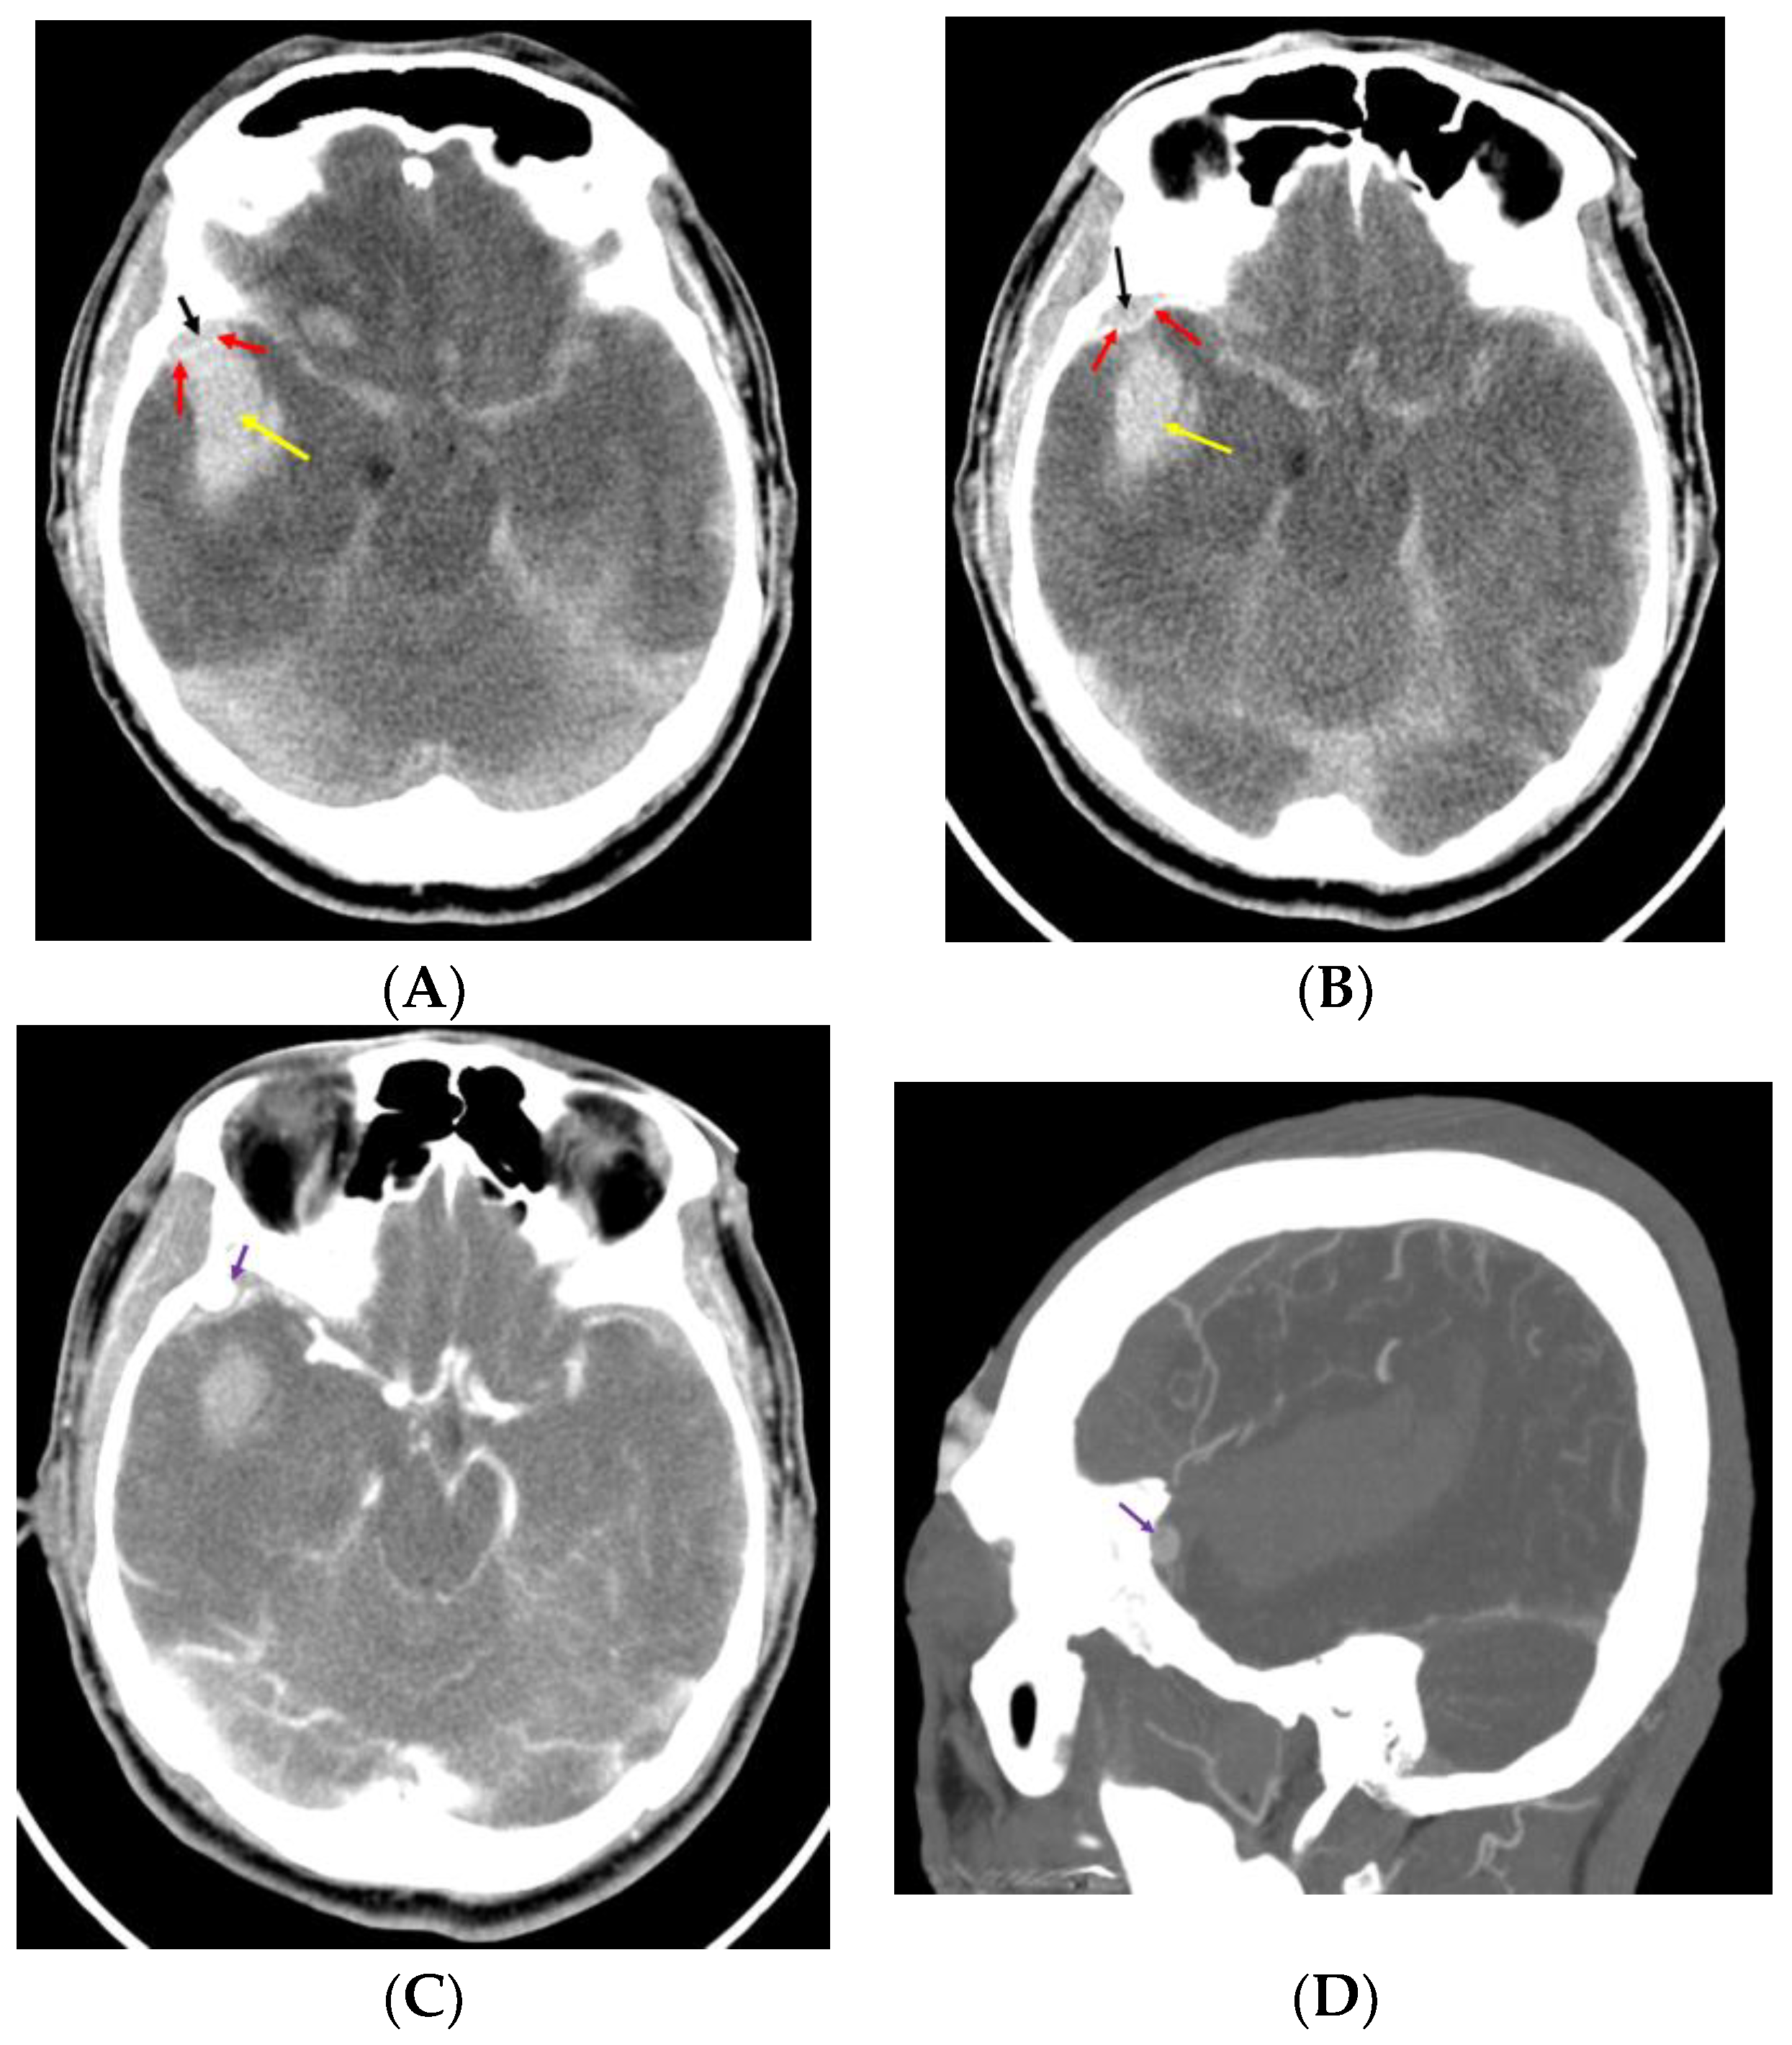

Rumbaugh et al. suggested that an SDH or ICH may result from the rupture of a pseudoaneurysm in the MMA, particularly if the dura has been torn; however, they did not present a case of dura tear resulting in ICH [44]. Kumar et al. and Moon et al. reported cases with an acute small EDH and ICH from the rupture of a pseudoaneurysm in the MMA after trauma [6,7] (Figure 1).

In both reports, the authors mentioned that brisk epidural bleeding during bone flap removal and dura tear were detected. Moon et al. proposed that the rupture of a pseudoaneurysm in the MMA in contact with a dural defect could cause ICH via the dura tear [6]. In situations where there is a dura tear, the rupture of a pseudoaneurysm located in the epidural space produces an EDH at the initial stage of the rupture and subsequently results in ICH via the dura tear. Figures 1 and 3 in Moon et al.’s report [6] demonstrate that the rupture of a pseudoaneurysm in the MMA with a dura tear results in a small EDH and acute ICH. Figure 2 illustrates a dura tear associated with a pseudoaneurysm in the MMA.

Figure 1. Preoperative computed tomography (CT) before (A,B) and after (C,D) contrast injection. Pre-contrast CTs demonstrate a small epidural hemorrhage (EDH) and intracerebral hemorrhage (ICH) (black arrow, EDH; red arrow, dura mater; yellow arrow, ICH). (A) ICH in contact with EDH. Post-contrast CTs (C,D) show a suspicious pseudoaneurysm located in the epidural space (violet arrow: suspicious pseudoaneurysm).